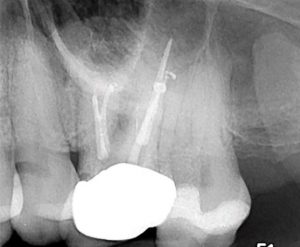

Eighteen months later, the patient returned for a second reassessment appointment (Figure 4 ). Tooth LR2 was slightly sensitive to percussion and the overlying gingival tissues were inflamed.

The patient was referred for a CBCT; the scan (Figure 5)

revealed a common area of rarefying osteitis surrounding the mesial buccal and distal buccal roots which had caused elevation of the sinus floor. As the endodontic pathology had not resolved, treatment options were proposed. The patient chose to have microsurgical therapy performed.